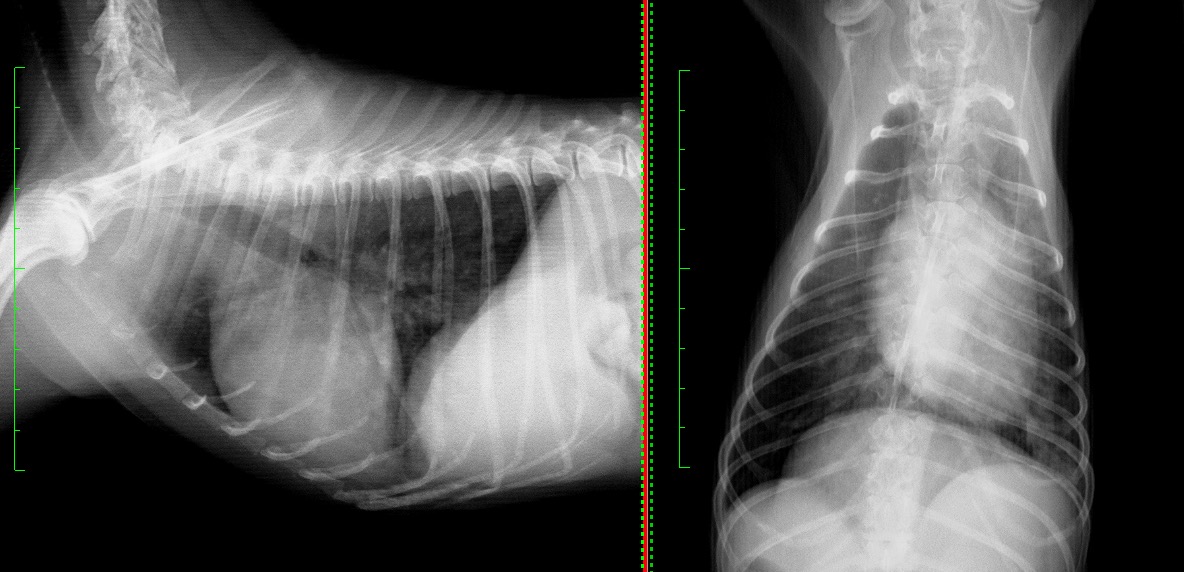

下に示すものがその時の胸部X線写真になります。 肺野が全体的に白くなり(不透過性の亢進)、その他検査と合わせ、肺炎の可能性が高いと診断し、すぐに入院下での治療を開始しました。